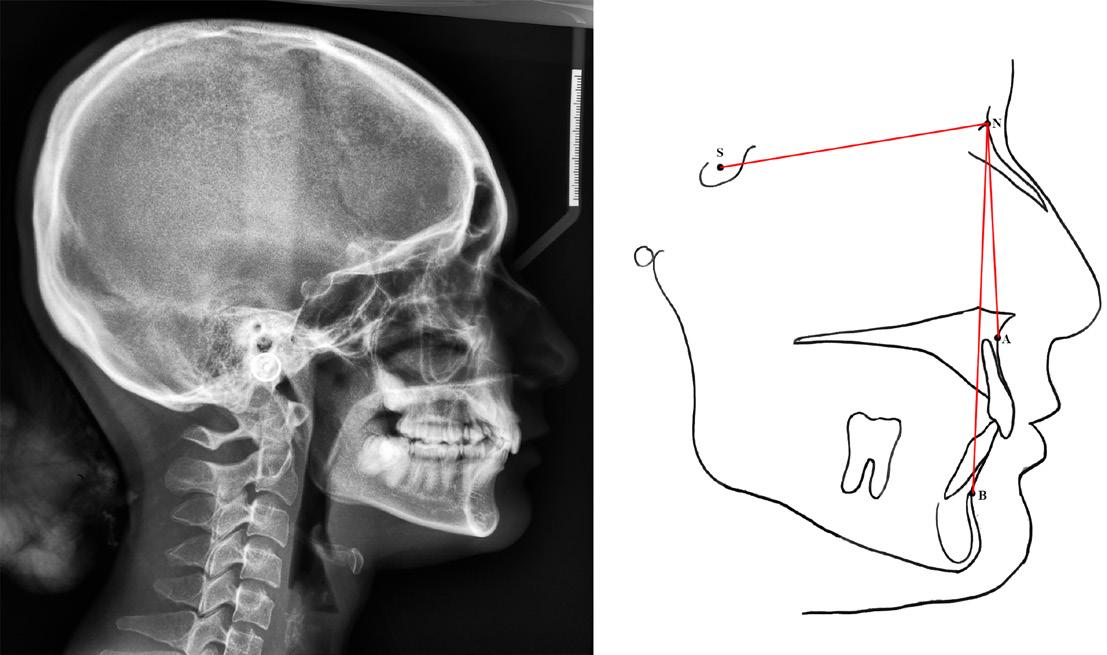

Identified subjects underwent comprehensive clinical examination by one of the researchers at IIUM Specialist Clinic to ensure no anomalies in tooth number, morphology and eruption. A lateral cephalometric radiograph was taken as a record for cephalometric analysis. Eastman analysis,12 measuring sellanasion-A-point angle (SNA), sella-nasion-B point angle (SNB), A point-nasion-B point (ANB) and the Wits appraisal (AoBo) were executed.13 The points as illustrates in Figure 1.

Figure 1: Reference points on the cephalometric radiograph: Sella (S)midpoint of the sella turcica, Nasion (N), A point (A)- deepest point of concavity on the anterior profile of the maxilla, B point (B)- deepest point of concavity on the anterior surface of the mandibular symphysis, Gonion (Go)- the most posterior, inferior point on the angle of the mandible, Menton (Me)- the most inferior point on the mandibular symphysis, Pogonion (Pog)- the most anterior point of the mandibular symphysis, Porion (Po)- the upper midpoint of the external auditory meatus, Anterior nasal spine (ANS), Posterior Nasal Spine (PNS). (Figure reprinted with permission from Siva Dharma D, Abu Bakar N, Mustafa BE. Evaluation of Salivary Leptin Levels and Its Correlation with Class I, Class II, and Class III Facial Skeletal Pattern: A Prefatory Study. European Journal of Dentistry. Published online August 24, 2021. doi:https://doi. org/10.1055/s-0041-1727552)

1. Cephalometric value indicative of Class I based on Eastman (ANB within 2°to 4°, SNA within range of 81°±3° and SNB within range of 78°±3°) as shown in Figure 2.

2. Wits appraisal (AoBo) within Class I (- 2mm to +2mm)

3. Straight facial profile

tracing (right) of a Class I lateral cephalometric radiograph (left). To calculate angles SNA and SNB, lines are drawn between the points S, N, and A. The ANB angle is obtained by deducting angle of SNB from SNA. (Figure reprinted with permission from Siva Dharma D, Abu Bakar N, Mustafa BE. Evaluation of Salivary Leptin Levels and Its Correlation with Class I, Class II, and Class III Facial Skeletal Pattern: A Prefatory Study. European Journal of Dentistry. Published online August 24, 2021. doi:https://doi.org/10.1055/s-0041-1727552)

Cephalometric analysis criteria for Class II facial skeletal pattern:

• Cephalometric analysis with value indicative of Class II based on Eastman analysis (ANB should be >4° and SNB should be <78°) as shown in Figure 3.

• SNA within normal range indicative of average maxilla (81°±3°)

• Positive Wits appraisal (AoBo > 2 mm)

• Convex facial profile

Figure 3: Cephalometric tracing (right) of a Class II lateral cephalometric radiograph (left). To calculate angles SNA and SNB, lines are drawn between the points S, N, and A. The ANB angle is obtained by deducting angle of SNB from SNA. (Figure reprinted with permission from Siva Dharma D, Abu Bakar N, Mustafa BE. Evaluation of Salivary Leptin Levels and Its Correlation with Class I, Class II, and Class III Facial Skeletal Pattern: A Prefatory Study. European Journal of Dentistry. Published online August 24, 2021. doi:https://doi.org/10.1055/s-0041-1727552)

Cephalometric analysis criteria for Class III facial skeletal pattern:

• Cephalometric analysis with value indicative of Class III based on Eastman analysis (ANB should be <2° and SNB should be >81°) as shown in Figure 4.

• Negative Wits appraisal (AoBo) of < - 2mm

• Concave facial profile

Figure 4: Cephalometric tracing (right) of a Class III lateral cephalometric radiograph (left). To calculate angles SNA and SNB, lines are drawn between the points S, N, and A. The ANB angle is obtained by deducting angle of SNB from SNA. (Figure reprinted with permission from Siva Dharma D, Abu Bakar N, Mustafa BE. Evaluation of Salivary Leptin Levels and Its Correlation with Class I, Class II, and Class III Facial Skeletal Pattern: A Prefatory Study. European Journal of Dentistry. Published online August 24, 2021. doi:https://doi.org/10.1055/s-0041-1727552)